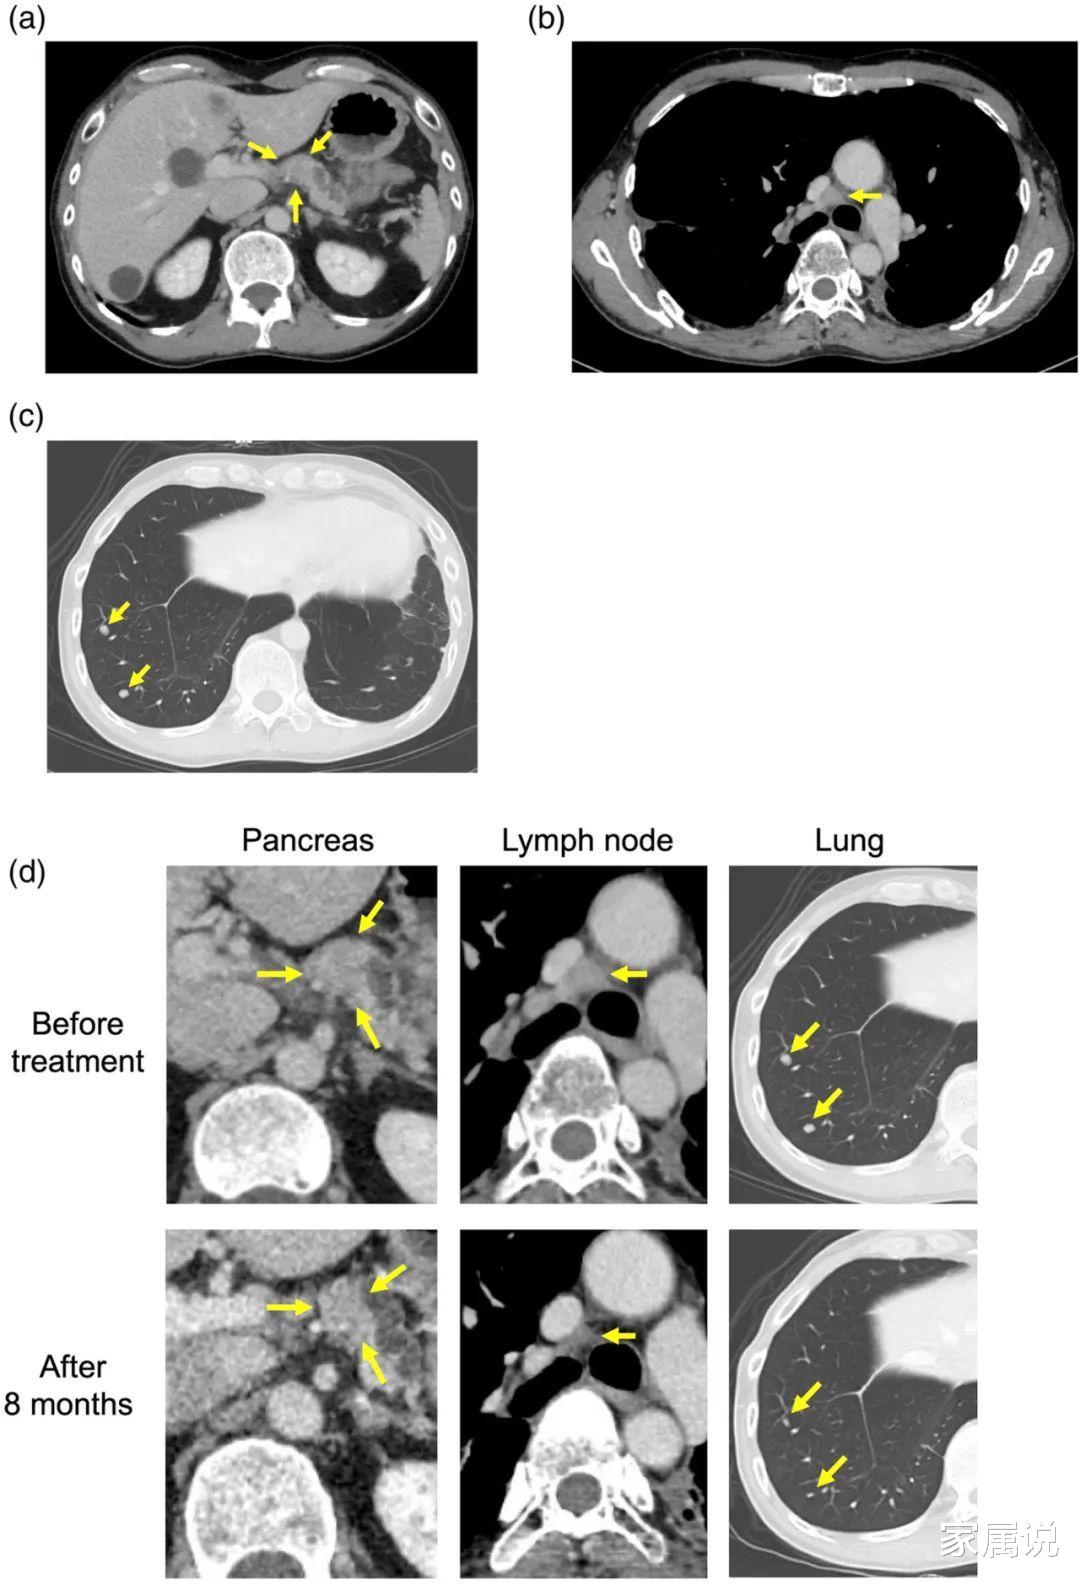

图注:(a)胰腺转移灶 , (b)纵隔淋巴结转移灶 , (c)阿法替尼单药治疗开始前肺右下叶转移灶 。 (d)阿法替尼治疗8个月前后胰腺、淋巴结和肺转移病灶的肿瘤缩小 。

对2017年获得的手术标本进行了基因检测 , 发现存在EGFR L858R和L747V突变伴随EGFR扩增和TP53 R196突变 。 患者开始接受起始剂量为40mg/天的阿法替尼 , 治疗后转移病灶消退 。 然而 , 由于无法忍受皮肤毒性 , 阿法替尼的剂量减少到20mg/天 。

在接受阿法替尼12个月治疗后 , 患者出现胰腺和右肺门淋巴结转移 。